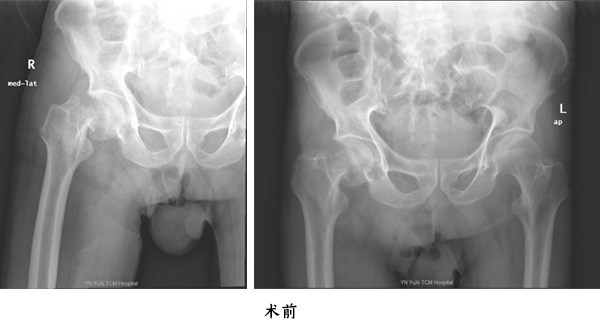

第一位為百歲老人張老太,因為在家中走路時跌倒致傷左髖部,傷后至當?shù)蒯t(yī)院就診,拍片檢查結果示左股骨頸骨折,后轉至我院住院治療;第二位百歲老人為王大爺,也是因為在家門口走路跌倒致傷右髖部,在當?shù)蒯t(yī)院就診拍片并診斷為右股骨頸骨折,后轉至我院住院治療。

由于高齡老人往往基礎病較多,全身器官如心、腦、肺等功能欠佳,如果施行手術風險極高,如果在病人管理上某一個環(huán)節(jié)出現(xiàn)問題就會隨時危及生命,高齡股骨頸骨折患者,如果采用保守治療,因為長期臥床而產生一些致命性的并發(fā)癥,入住玉溪市中醫(yī)醫(yī)院骨傷二科(關節(jié)與運動醫(yī)學科)后,經科室團隊詳細制定治療計劃,麻醉科會診,分別于2020年12月8日及2020年12月4日為兩名百歲老人施行人工股骨頭置換手術,手術過程順利,通過該手術,兩名百歲老人再次站起來下地步行,均順利康復出院。